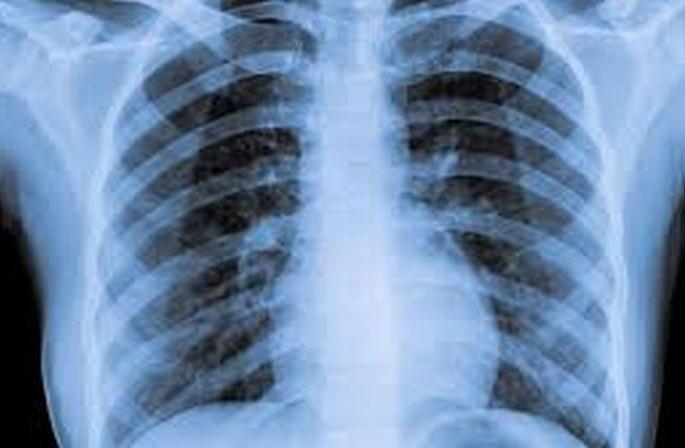

संदिग्ध रुग्ण आढल्यास त्याच्या शरीरातील आॅक्सीन लेव्हल तपासण्यासोबतच त्याचा एक्सरेही काढण्यात येणार आहे.

बुलडाणा/मलकापूर : कोरोना संसर्गाचा उद्रेक सुरू झालेल्या मलकापूर शहरात प्रशासनाने प्रो अॅक्टीव भूमिका घेतली असून ११ कंटेन्मेंट झोनमध्ये संदिग्ध रुग्ण आढल्यास त्याच्या शरीरातील आॅक्सीन लेव्हल तपासण्यासोबतच त्याचा एक्सरेही काढण्यात येणार आहे.

प्रशासकीय पातळीवर तशा हालचाली सुरू झाल्या असल्याची माहिती सुत्रांनी दिली. मलकापूर तालुक्यात आतापर्यंत ४८ कोरोना बाधीत आढळून आले असून यातील १८ जण कोरोना मुक्त झाले आहेत. शहरात ६० हजार नागरिकांचा रॅपीड सर्व्हे ही करण्यात आला आहे. १५ जून रोजी एकाचवेळी तालुक्यात ११ कोरोना पॉझिटिव्ह रुग्ण आढळल्याच्या पार्श्वभूमीवर आता येथील कथितस्तरावरील समुह संक्रमण रोखण्यासाठी प्रशासन सक्रीय झाले आहे. त्यानुषंगाने शहरातील ११ ही कंटेन्मेंट झोनमधील नागरिकांच्या शरीरातील आॅक्सीजन लेव्हल आणि गरज पडल्यास त्यांचा एक्सरे जागेवरच काढण्याची भूमिका जिल्हा प्रशासनाने घेतली आहे.